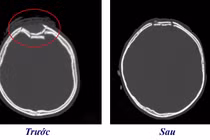

Bé trai ở Lào Cai bị chó cắn lộ xương sọ Sức khoẻ 360 19/07/2025 10:10 Một bé trai 3 tuổi ở Lào Cai bị chó nhà hàng xóm tấn công, cắn đứt tĩnh mạch, rách da đầu làm lộ hộp sọ, chấn thương phần mềm, phải nhập viện cấp cứu.